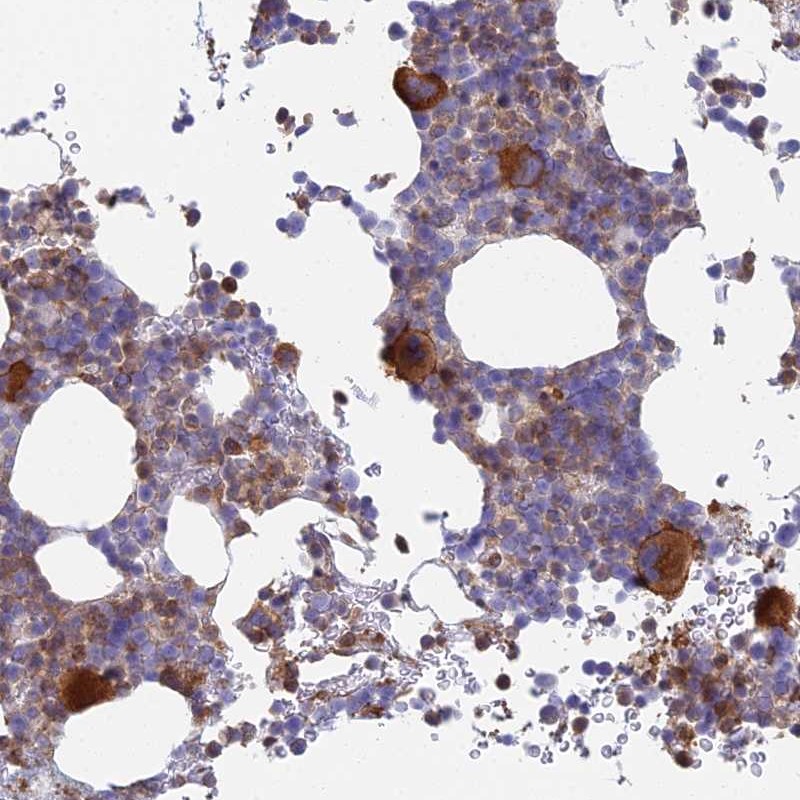

Immunohistochemical staining of human bone marrow shows strong cytoplasmic positivity in megakaryocytes.